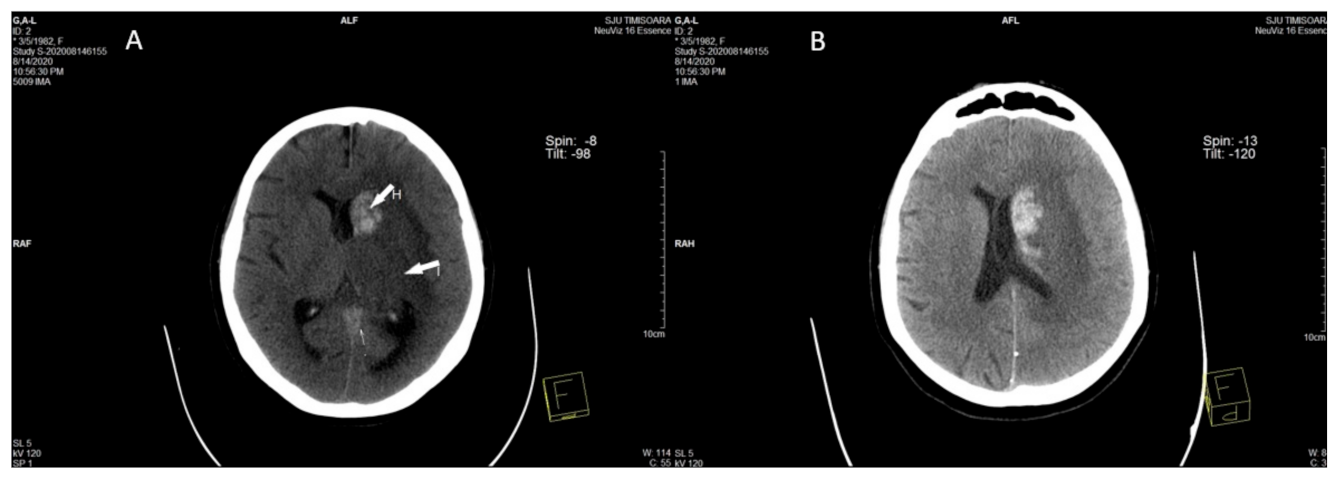

2.2. Imaging